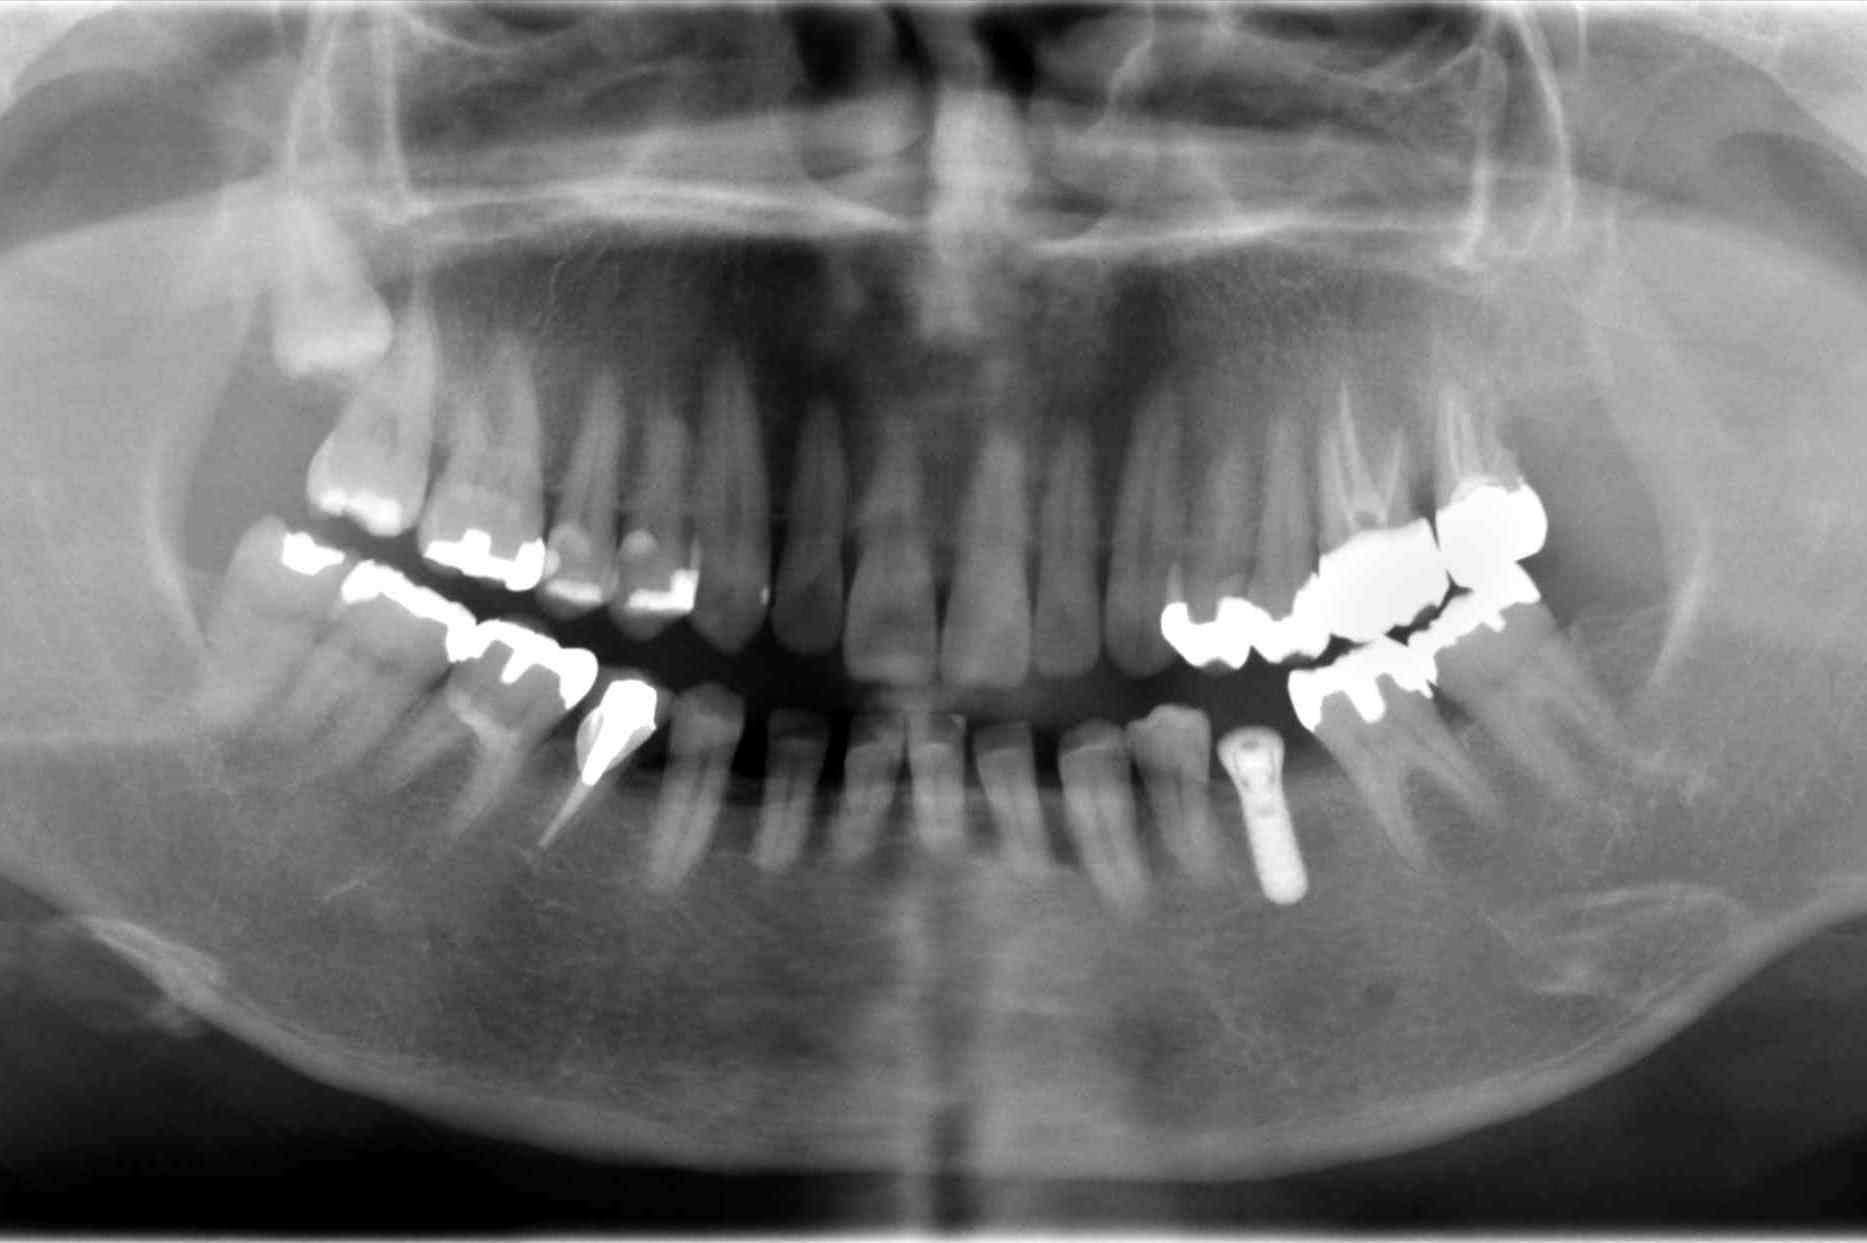

インプラント(人工の歯根)を入れた症例です。

歯の根っこにひびが入り、抜歯となった左下にインプラント(人工の歯根)を使って歯を入れました

前後の歯を削らずにすみます